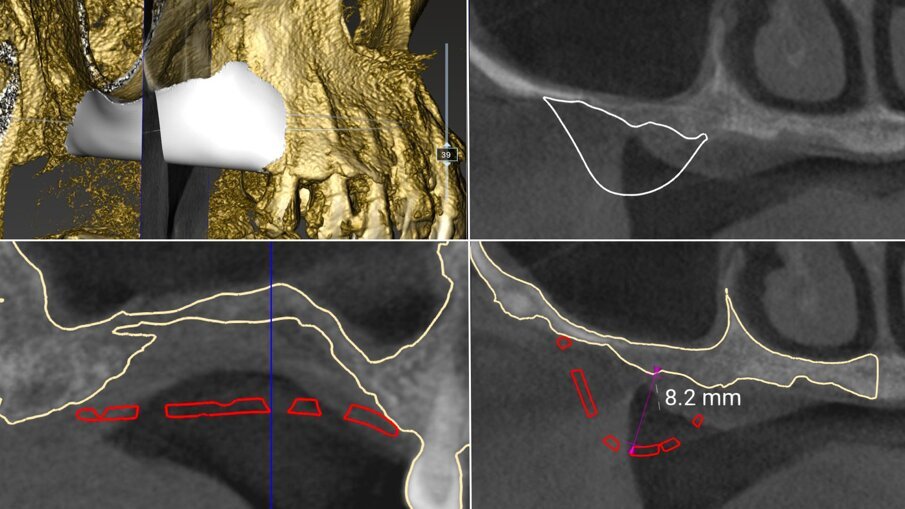

Il piano di trattamento è stato sviluppato utilizzando un flusso di lavoro completamente digitale. Pertanto, i files .DICOM ottenuti dalla CBCT pre-operatoria sono stati utilizzati per generare una ricostruzione 3D del mascellare, che ha permesso di eseguire la progettazione virtuale del volume osseo “ideale” per l’inserimento di 3 impianti in sede #15, #16, e #17. (Figg. 4, 5). Successivamente, è stata creata virtualmente la griglia customizzata corrispondente al volume aumentato nel mascellare della paziente (Fig. 6). Il giorno della chirurgia ricostruttiva (T0), è stata eseguita una profilassi antibiotica (2 g di amoxicillina con acido clavulanico e 500 mg di metronidazolo), una profilassi antinfiammatoria (20 mg di piroxicam), una sedazione cosciente x os (2 ml di delorazepam e 2 ml di diazepam), e disinfezione del cavo orale (risciacquo orale con povidone-iodio per un minuto, perossido di idrogeno per due minuti, e collutorio alla clorexidina 0,2% per tre minuti), e un’anestesia locale mediante articaina 4% contenente adrenalina 1:100.00018. L’esame obiettivo mostra la gravità del difetto osseo che determina un evidente difetto di volume sia in senso orizzontale che in senso verticale (Figg. 7, 8).